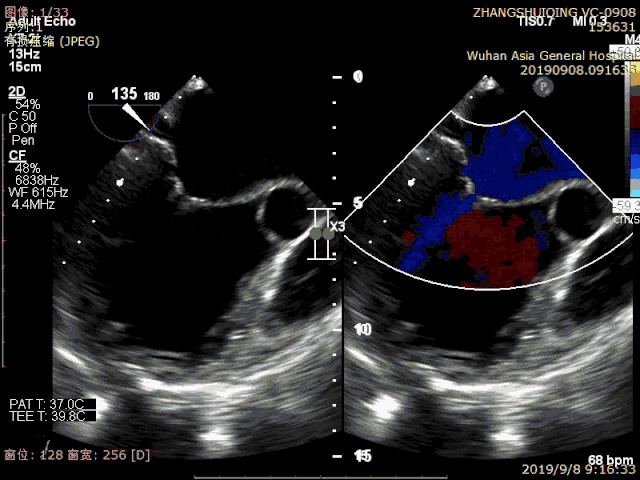

患者术前心超显示极重度反流

患者术前心超显示心脏扩大,严重脱垂